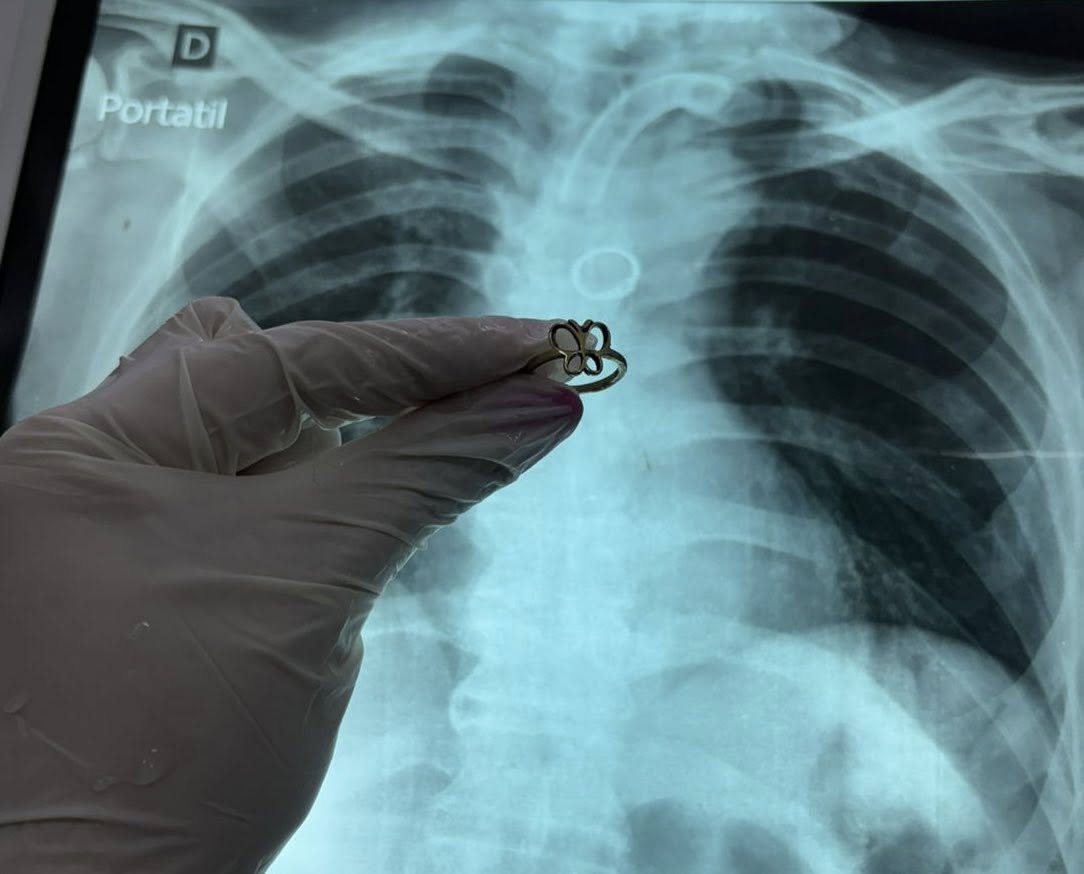

Un hallazgo tan inusual como inquietante se registró en el Instituto Nacional de Enfermedades Respiratorias y del Ambiente (INERAM), donde médicos detectaron y extrajeron un anillo de oro alojado en el pulmón de un paciente de 54 años.

Como parte del protocolo, se le practicó una radiografía de control. Fue entonces cuando apareció una imagen extraña: una figura circular en el bronquio fuente izquierdo.

El neumólogo Carlos Morinigo relató el caso, señalando que el equipo médico se encontró con “lo impensado”: un anillo de oro de tamaño considerable alojado en el pulmón.

Ante la situación, los especialistas optaron por retirar la cánula traqueal e ingresar con un broncoscopio rígido por la vía oral. Finalmente, lograron ubicar y extraer el objeto.

“El anillo estaba brillando donde nunca debería estar”, describió el médico.